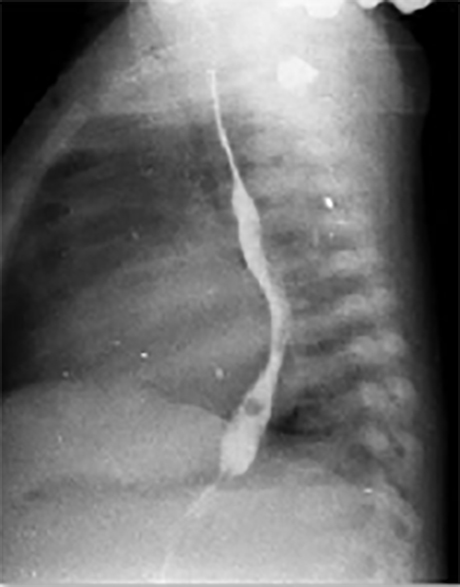

Another Patient

PA and Lateral

Click on the xrays to enlarge them.

Choose the best interpretation of the chest X rays:

RV enlargement, dilated

pulmonary trunk, increased pulmonary

arterial vascularity

LA/biventricular enlargement,increased pulmonary arterialvascularity

LV enlargement, aortic dilatation

RV hypertrophy, smallpulmonary trunk, decreasedpulmonary arterialvascularity

Dilated pulmonary trunk, normal vascularity